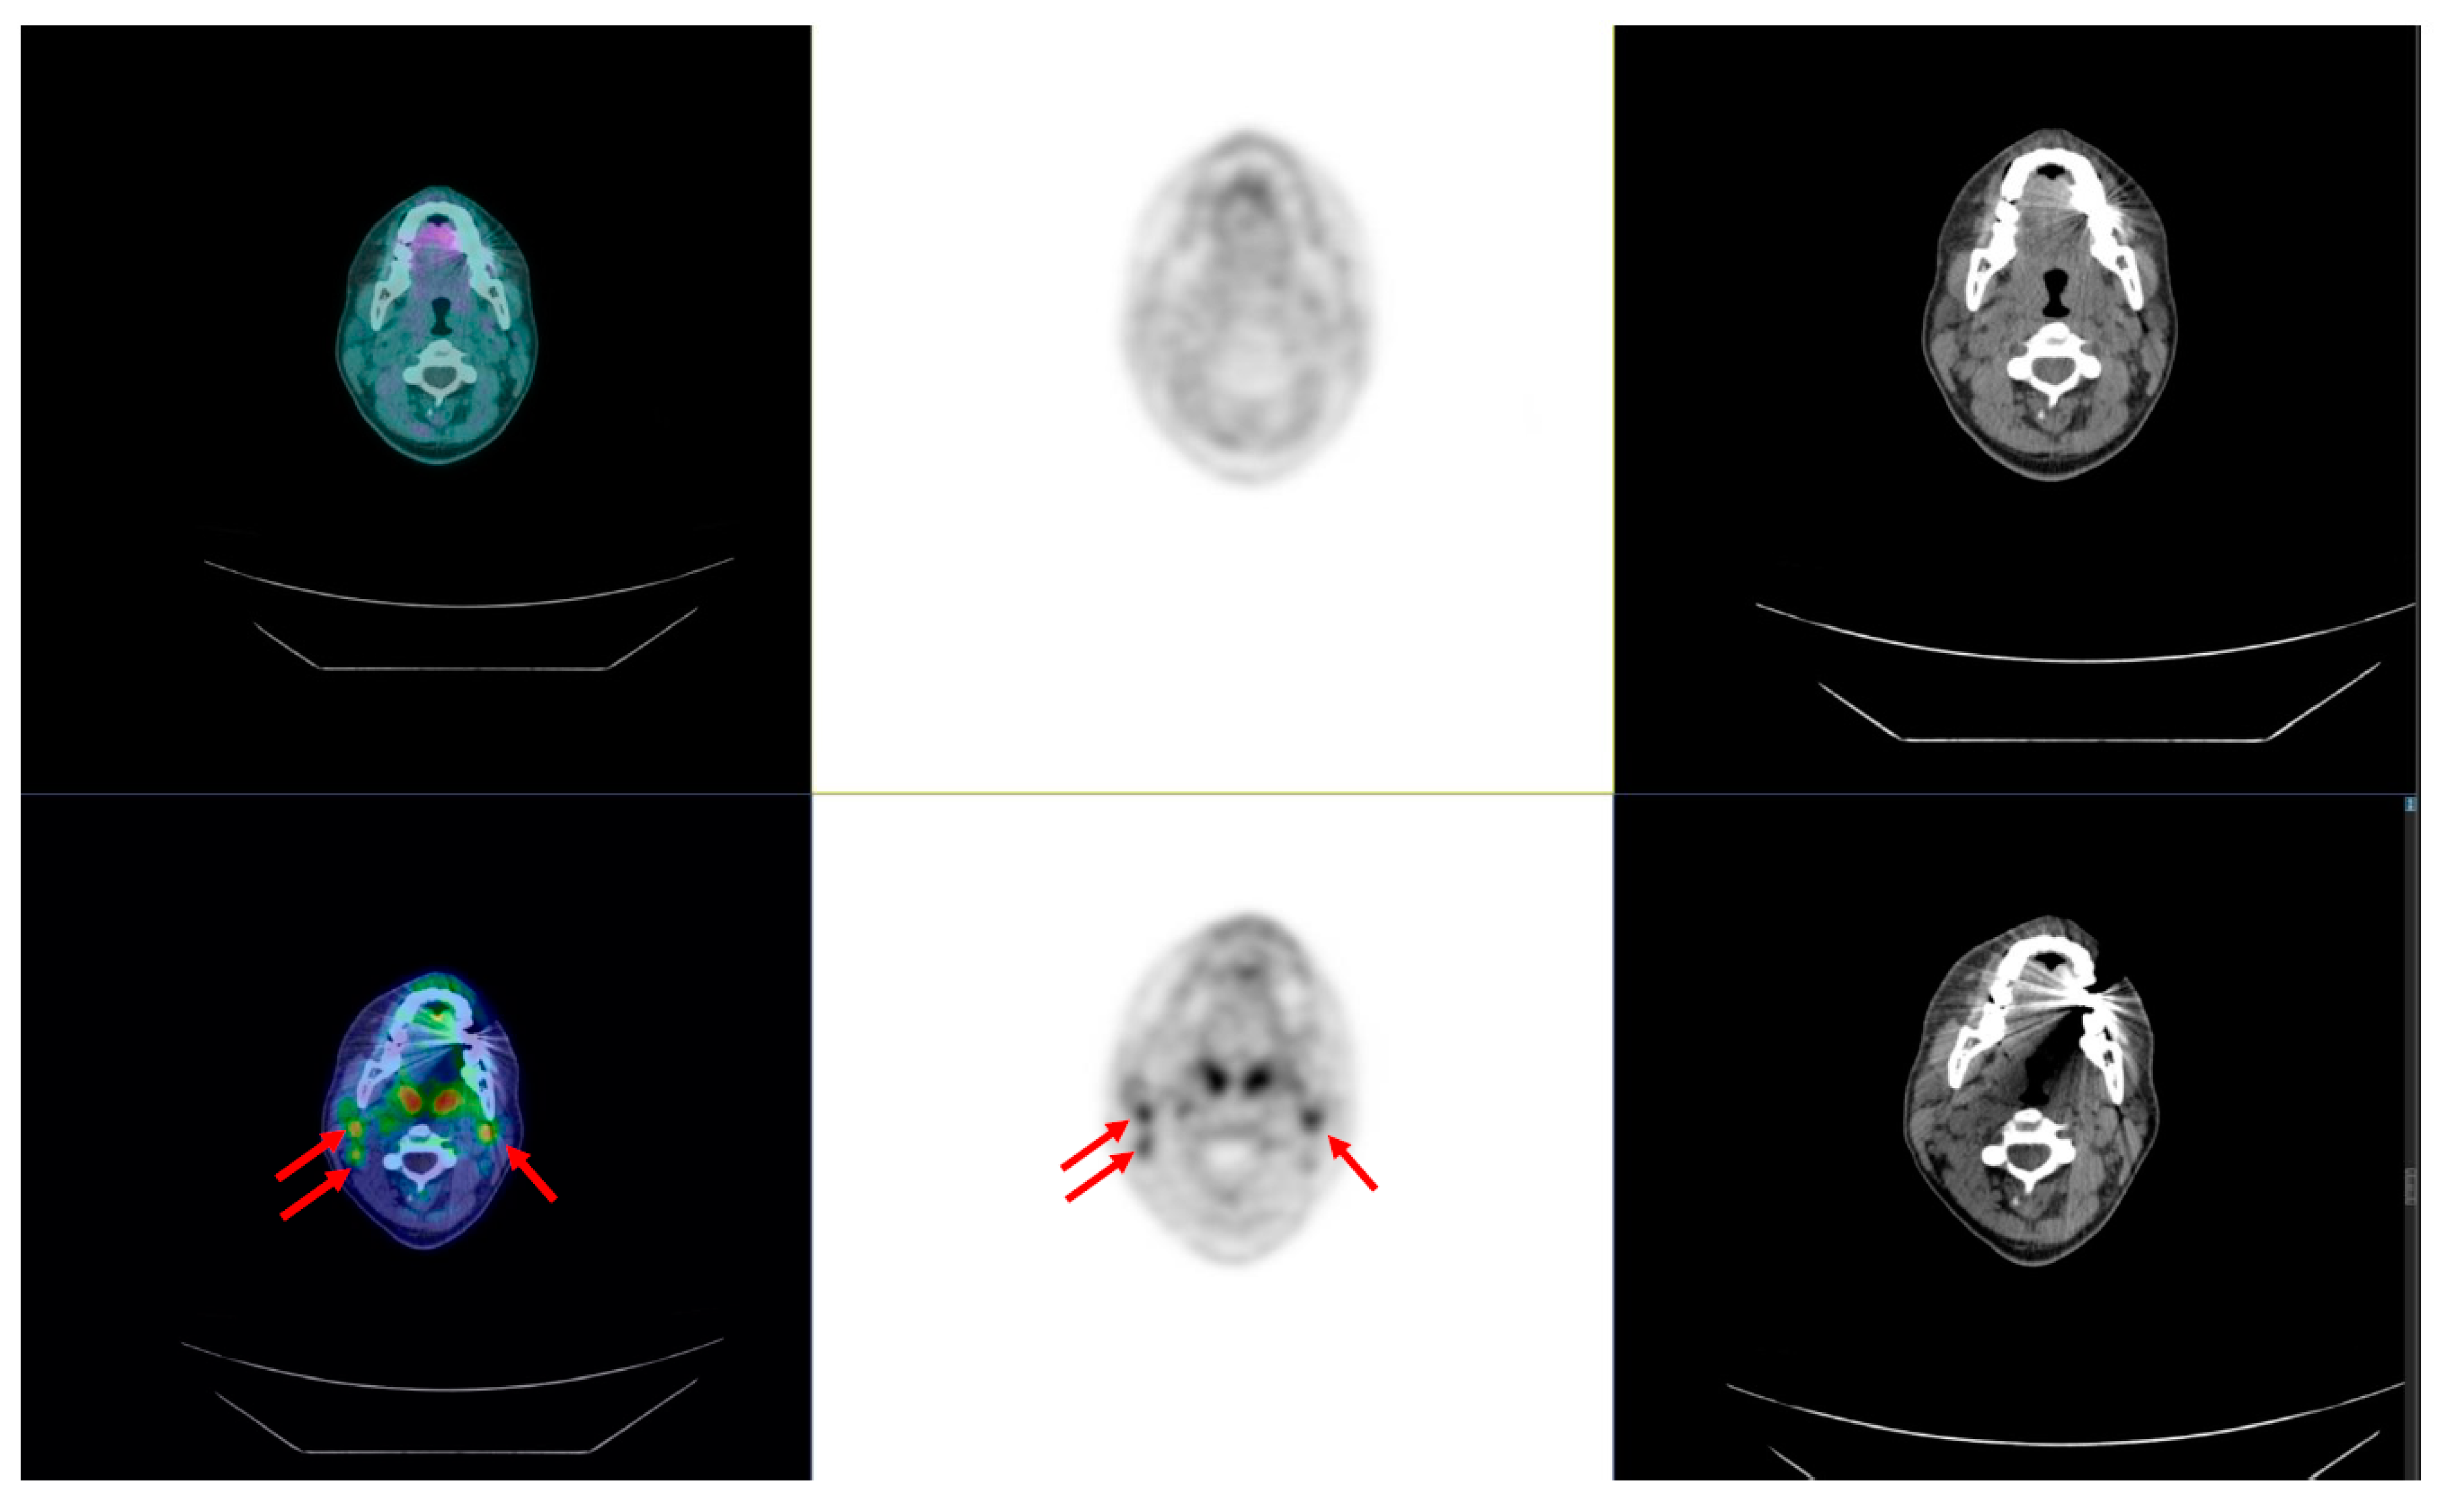

7.3. Molecular Imaging and Theragnostics